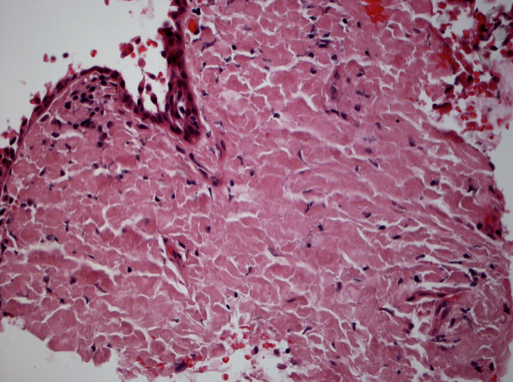

Figure 3: Conjunctival amyloidosis.

Same patient in Figure 2, showing hematoxylin and eosin stain of conjunctival tissue biopsy. Extensive hyalinization and diffuse eosinophilic extracellular material consistent with amyloidosis. (Image courtesy of Paul J. Bryar, MD)